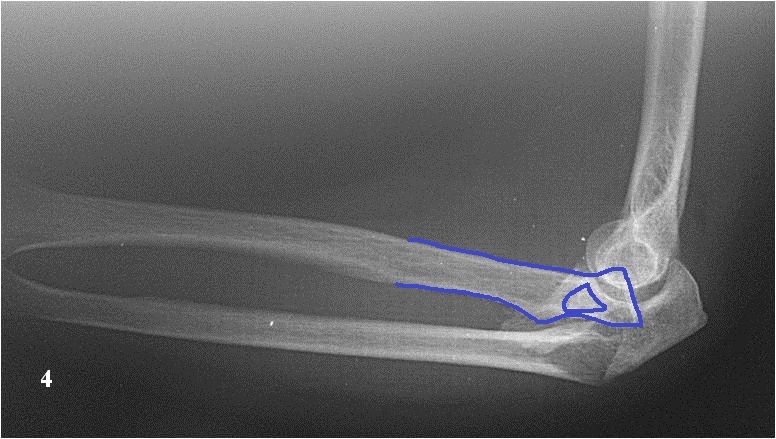

Хочу попросить совета у сообщества по поводу следующего клинического случая. Женщина, 65 лет. Закрытый перелом Монтеджи слева в октябре 2013 года. (рис. 1, 2). Для наглядности сделал скиаграмму перелома (рис. 3, 4). На 8-е сутки накостный остеосинтез пластинами с угловой стабильностью. Головка луча была восстановлена из отломков (рис. 5) и собрана на спицах одну из которых скусили и оставили под пластиной.(рис. 6). Вроде получилось стабильно, видео на операции по этой ссылке: